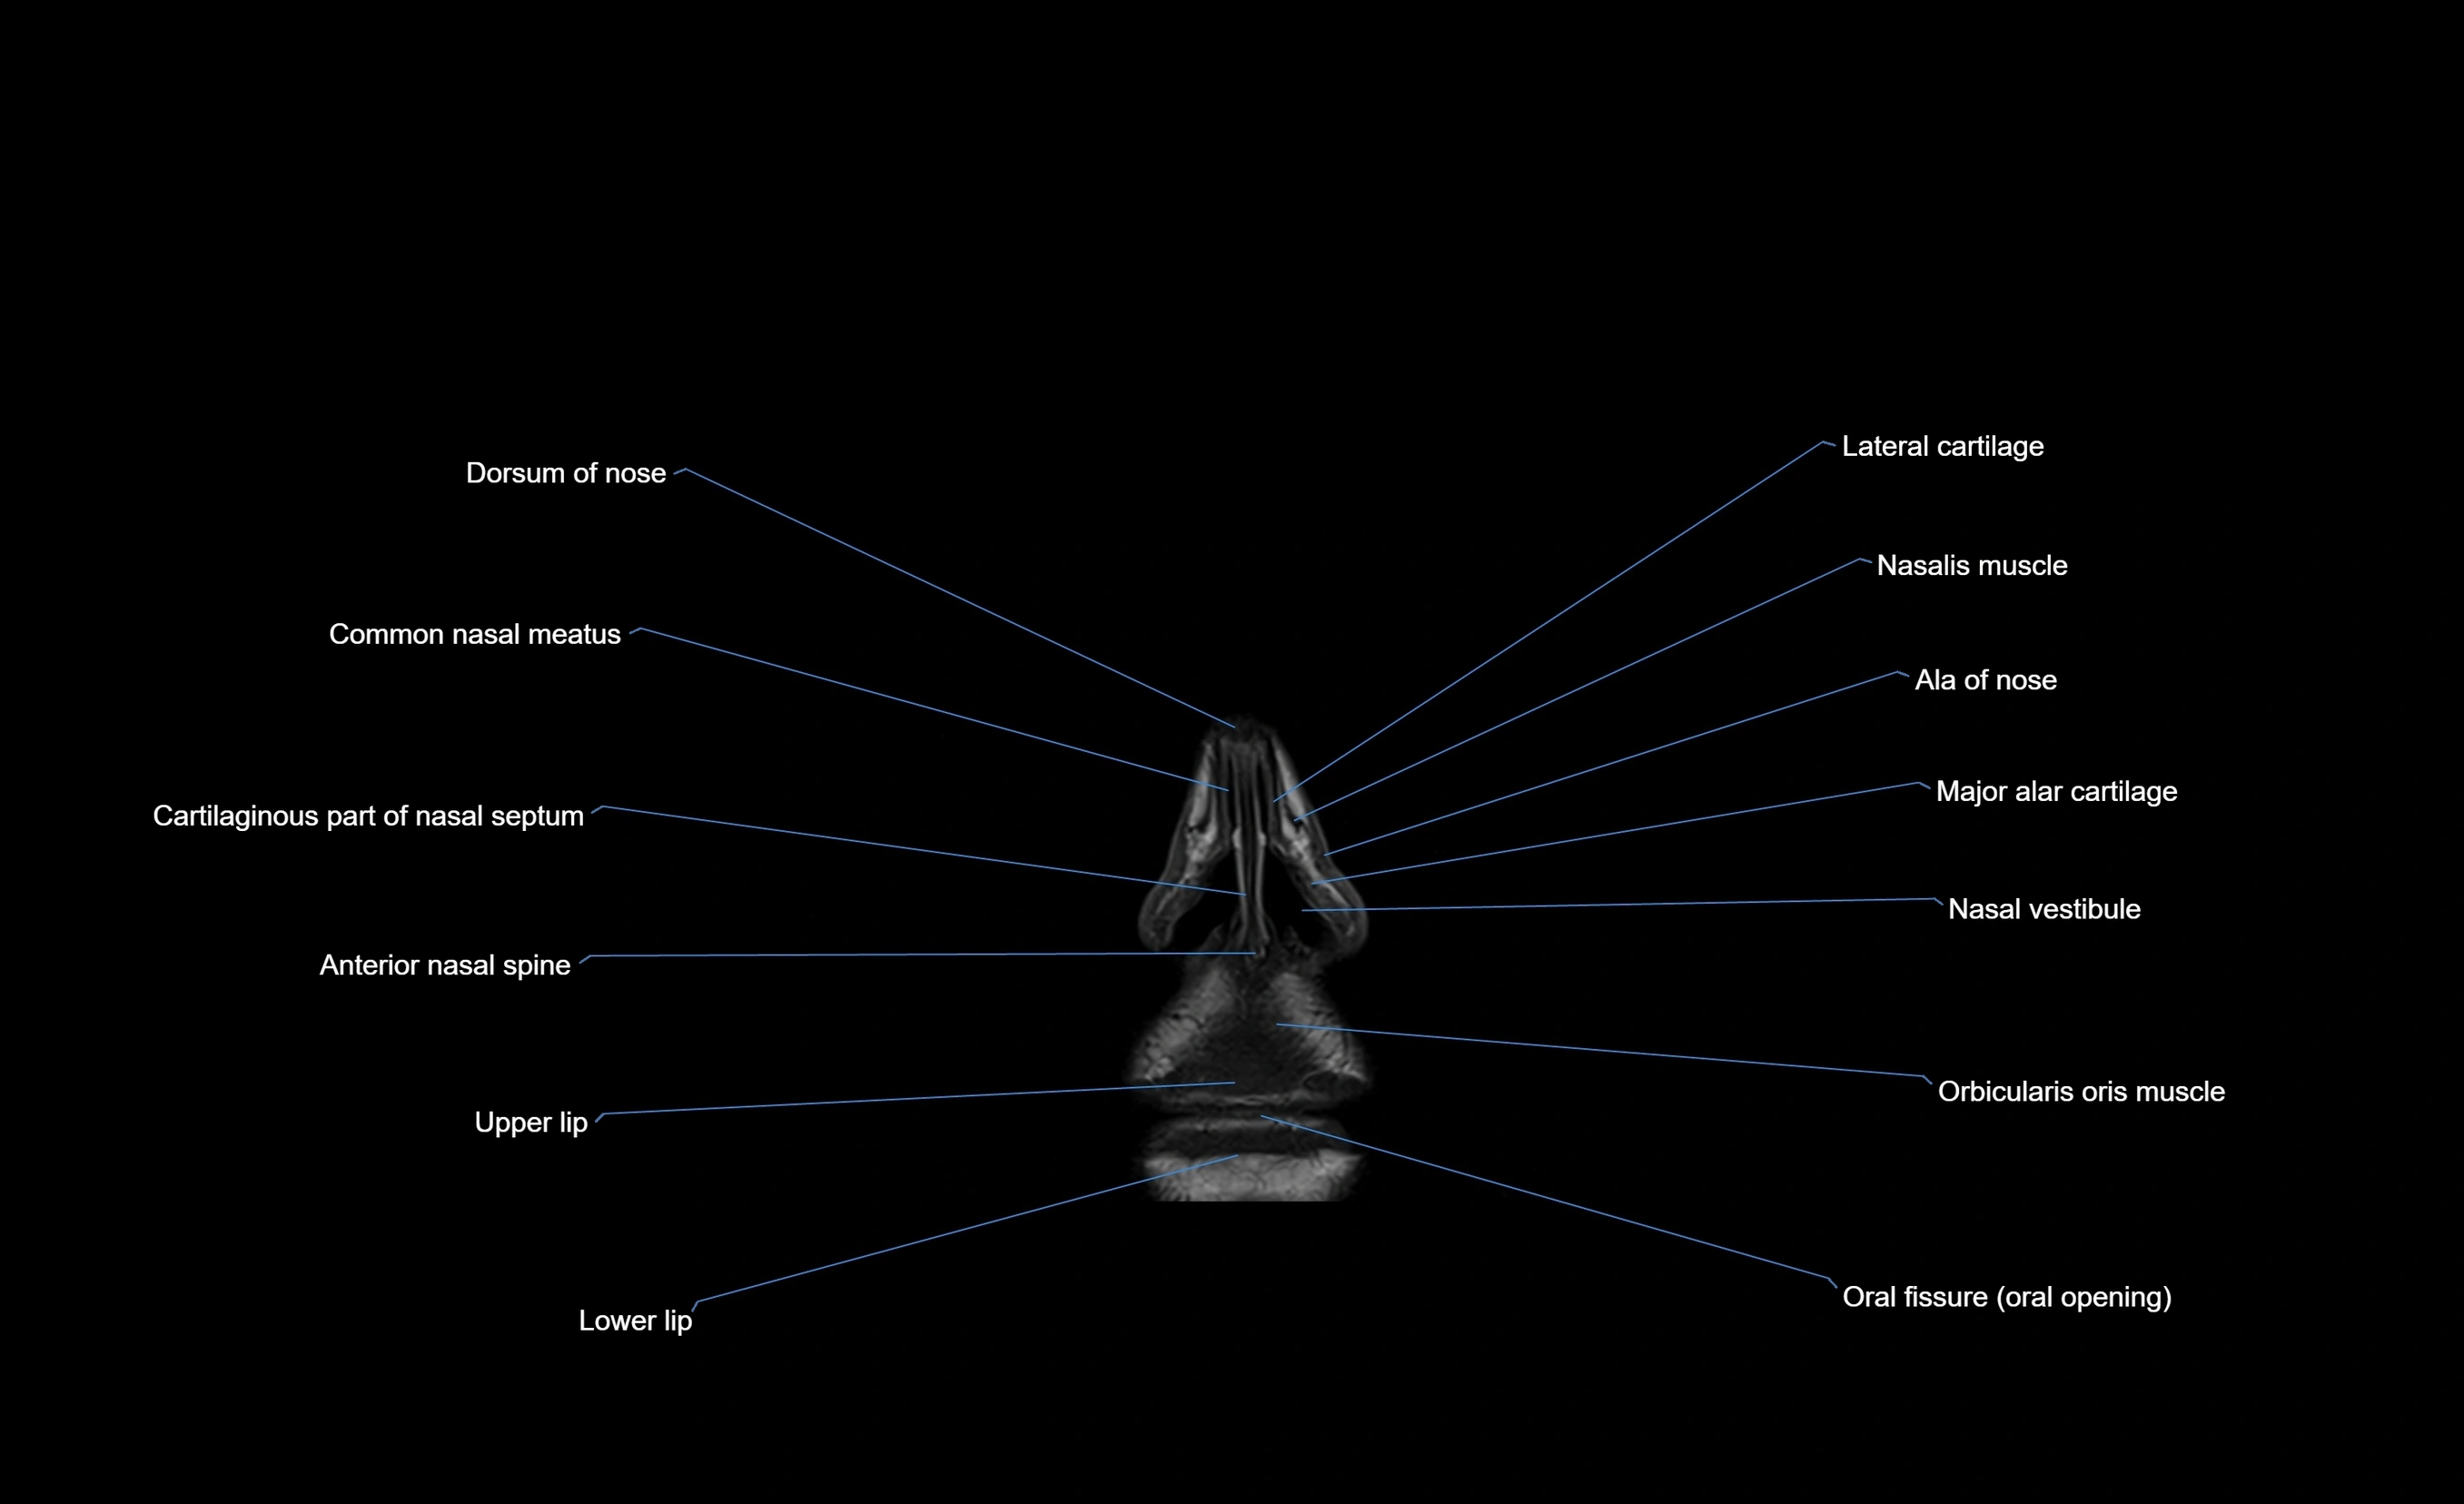

- Anterior nasal spine

- Cartilaginous part of nasal septum

- Common nasal meatus

- Dorsum of nose

- Greater alar cartilage

- Major alar cartilage

- Nasal vestibule

- Nasalis muscle

- Orbicularis oris muscle

- Lower lip